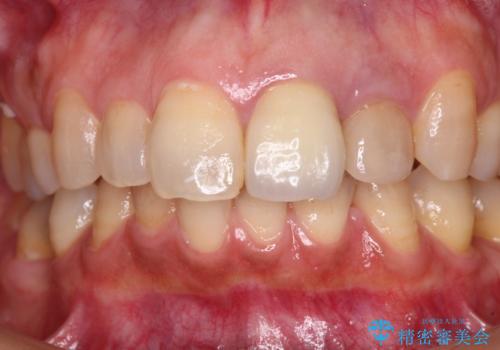

真ん中のオールセラミッククラウンを正面から見ると大変自然に仕上がっているのですが、側方から見ると白色が強く、さらには隣の歯は神経が除去されて変色していたため、コントラストでより色の違いが際立っていました。

前歯2本をオールセラミッククラウンにて補綴治療することとしました。